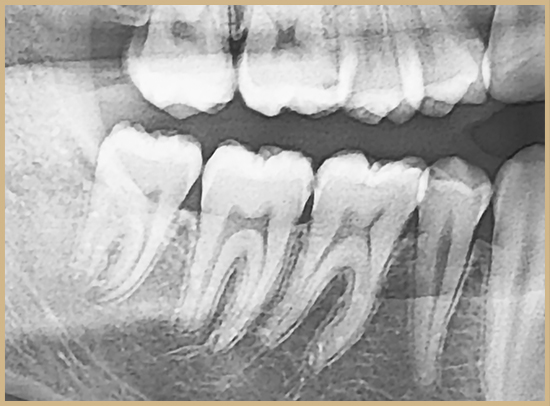

충치는 초기에는 특별한 증상 없이 조용히 진행되며,

눈에 띄지 않는 부위까지 빠르게 퍼질 수 있습니다.

특히 치아 뒷면이나 잇몸 선 근처처럼 외부에서 잘 보이지 않는 부분에 침투해도

통증이 없어 쉽게 지나치기 쉽습니다.

이처럼 자각 없이 진행되는 충치는 일상적인 관리만으로는

발견이 어려워 더 큰 손상을 유발할 수 있습니다.

3D CT 및 근관 확대경을 활용해 손상 범위를 파악하고,

자연 치아를 최대한 보존하는 방향으로 치료를 계획합니다.